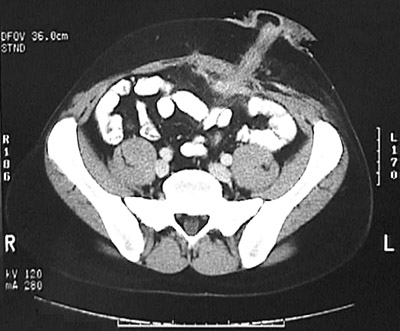

| A colostomy with stoma appears in this abdominal CT scan view from a patient who had granulomatous colitis most consistent with Crohn's disease and who developed a fistulous tract adjacent to the stoma. Transmural inflammation with Crohn's disease predisposes to fistula formation. |